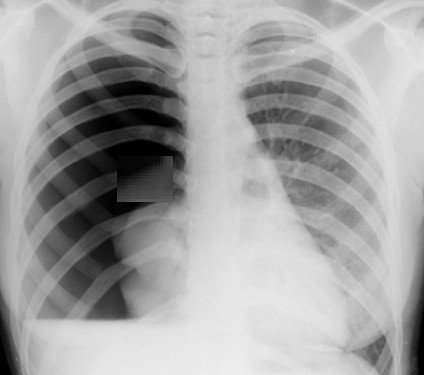

Pnömotoraks hacim hesabı nasıl yapılır?

Pnömotoraks Hacim Hesabı: